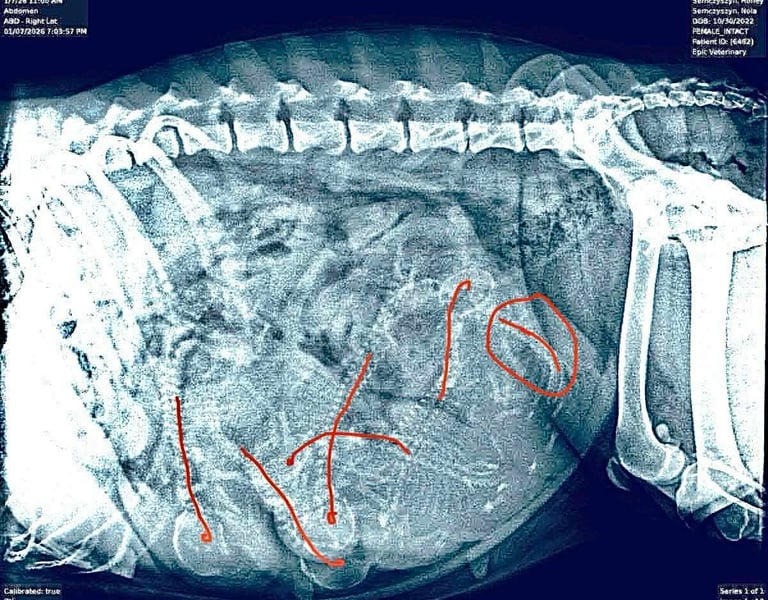

Update: 10 January 2026. Six puppies confirmed on X-Ray. We will be welcoming a new batch of Snarfs early next week.